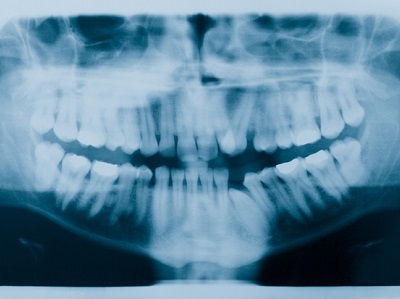

Also known as forensic odontologists, these professionals compare dental records from before and after death to determine human identity.

The work of odontologists includes the analysis of teeth, hard and soft tissues of the mouth, dental appliances, and possibly other identifying structures of the skull and lower jaw, using written records, x-rays and a visual examination.